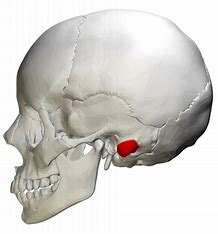

Styloid process (“stake like” point of attachment for several tongue and neck muscles)

Mastoid process (anchoring site for several neck muscles)